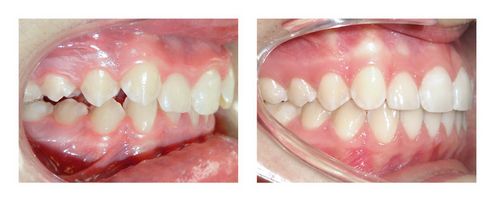

Cas 22 : Stimulation de la croissance mandibulaire avec des élastiques

La mâchoire inférieure de notre patiente n’avait pas assez grandi. Les arcades dentaires étaient décalées (surtout à droite) et les lèvres sous tension au repos.

Les incisives inférieures étant inclinées vers l’arrière, il a été possible de corriger le décalage grâce à des élastiques qui ont reculé les dents supérieures, avancé les dents inférieures et stimulé la croissance de la mâchoire inférieure. Après 2 ans de traitement, un bon emboitement a été ainsi obtenu et le profil s’est équilibré grâce à la bonne coopération de la patiente.